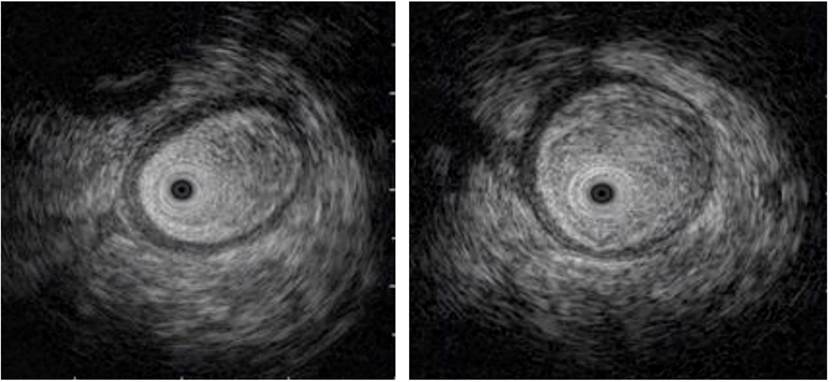

The study was complemented by an echo-endoscopy (Figure 4), in which the presence of edema of the loop wall was determined. Given these findings, radiation enteritis was highly suspected, and the patient was reassessed by the gastrointestinal surgery service, where it was considered that, in the event of non-improvement, he could benefit from surgical management. Therefore, a remodeling of the anastomosis was performed, and no tumor relapse was described in the histopathology report.